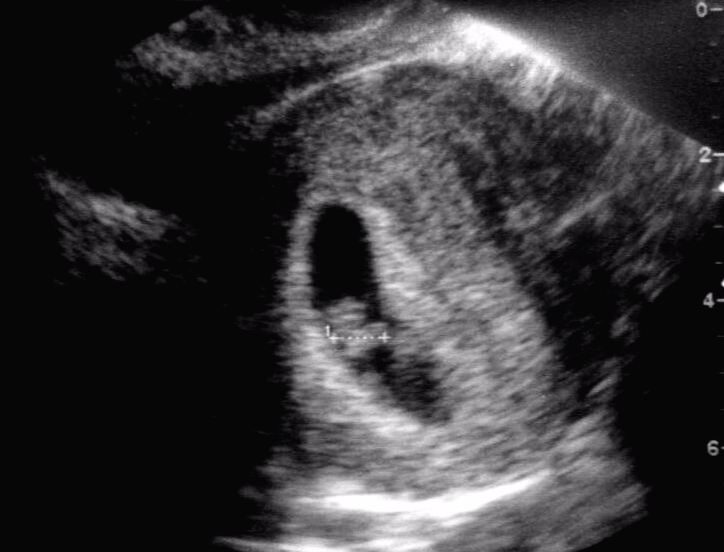

저희 아이가 커가는 과정의 초음파 사진입니다.

1cm의 아기집만 볼 수 있던 초음파 사진에서

어느덧 얼굴 윤곽을 확인할 수 있을 정도로 성장하여

임신 이후 12주 차가 되면

정밀초음파 검사를 하게 되는데요.